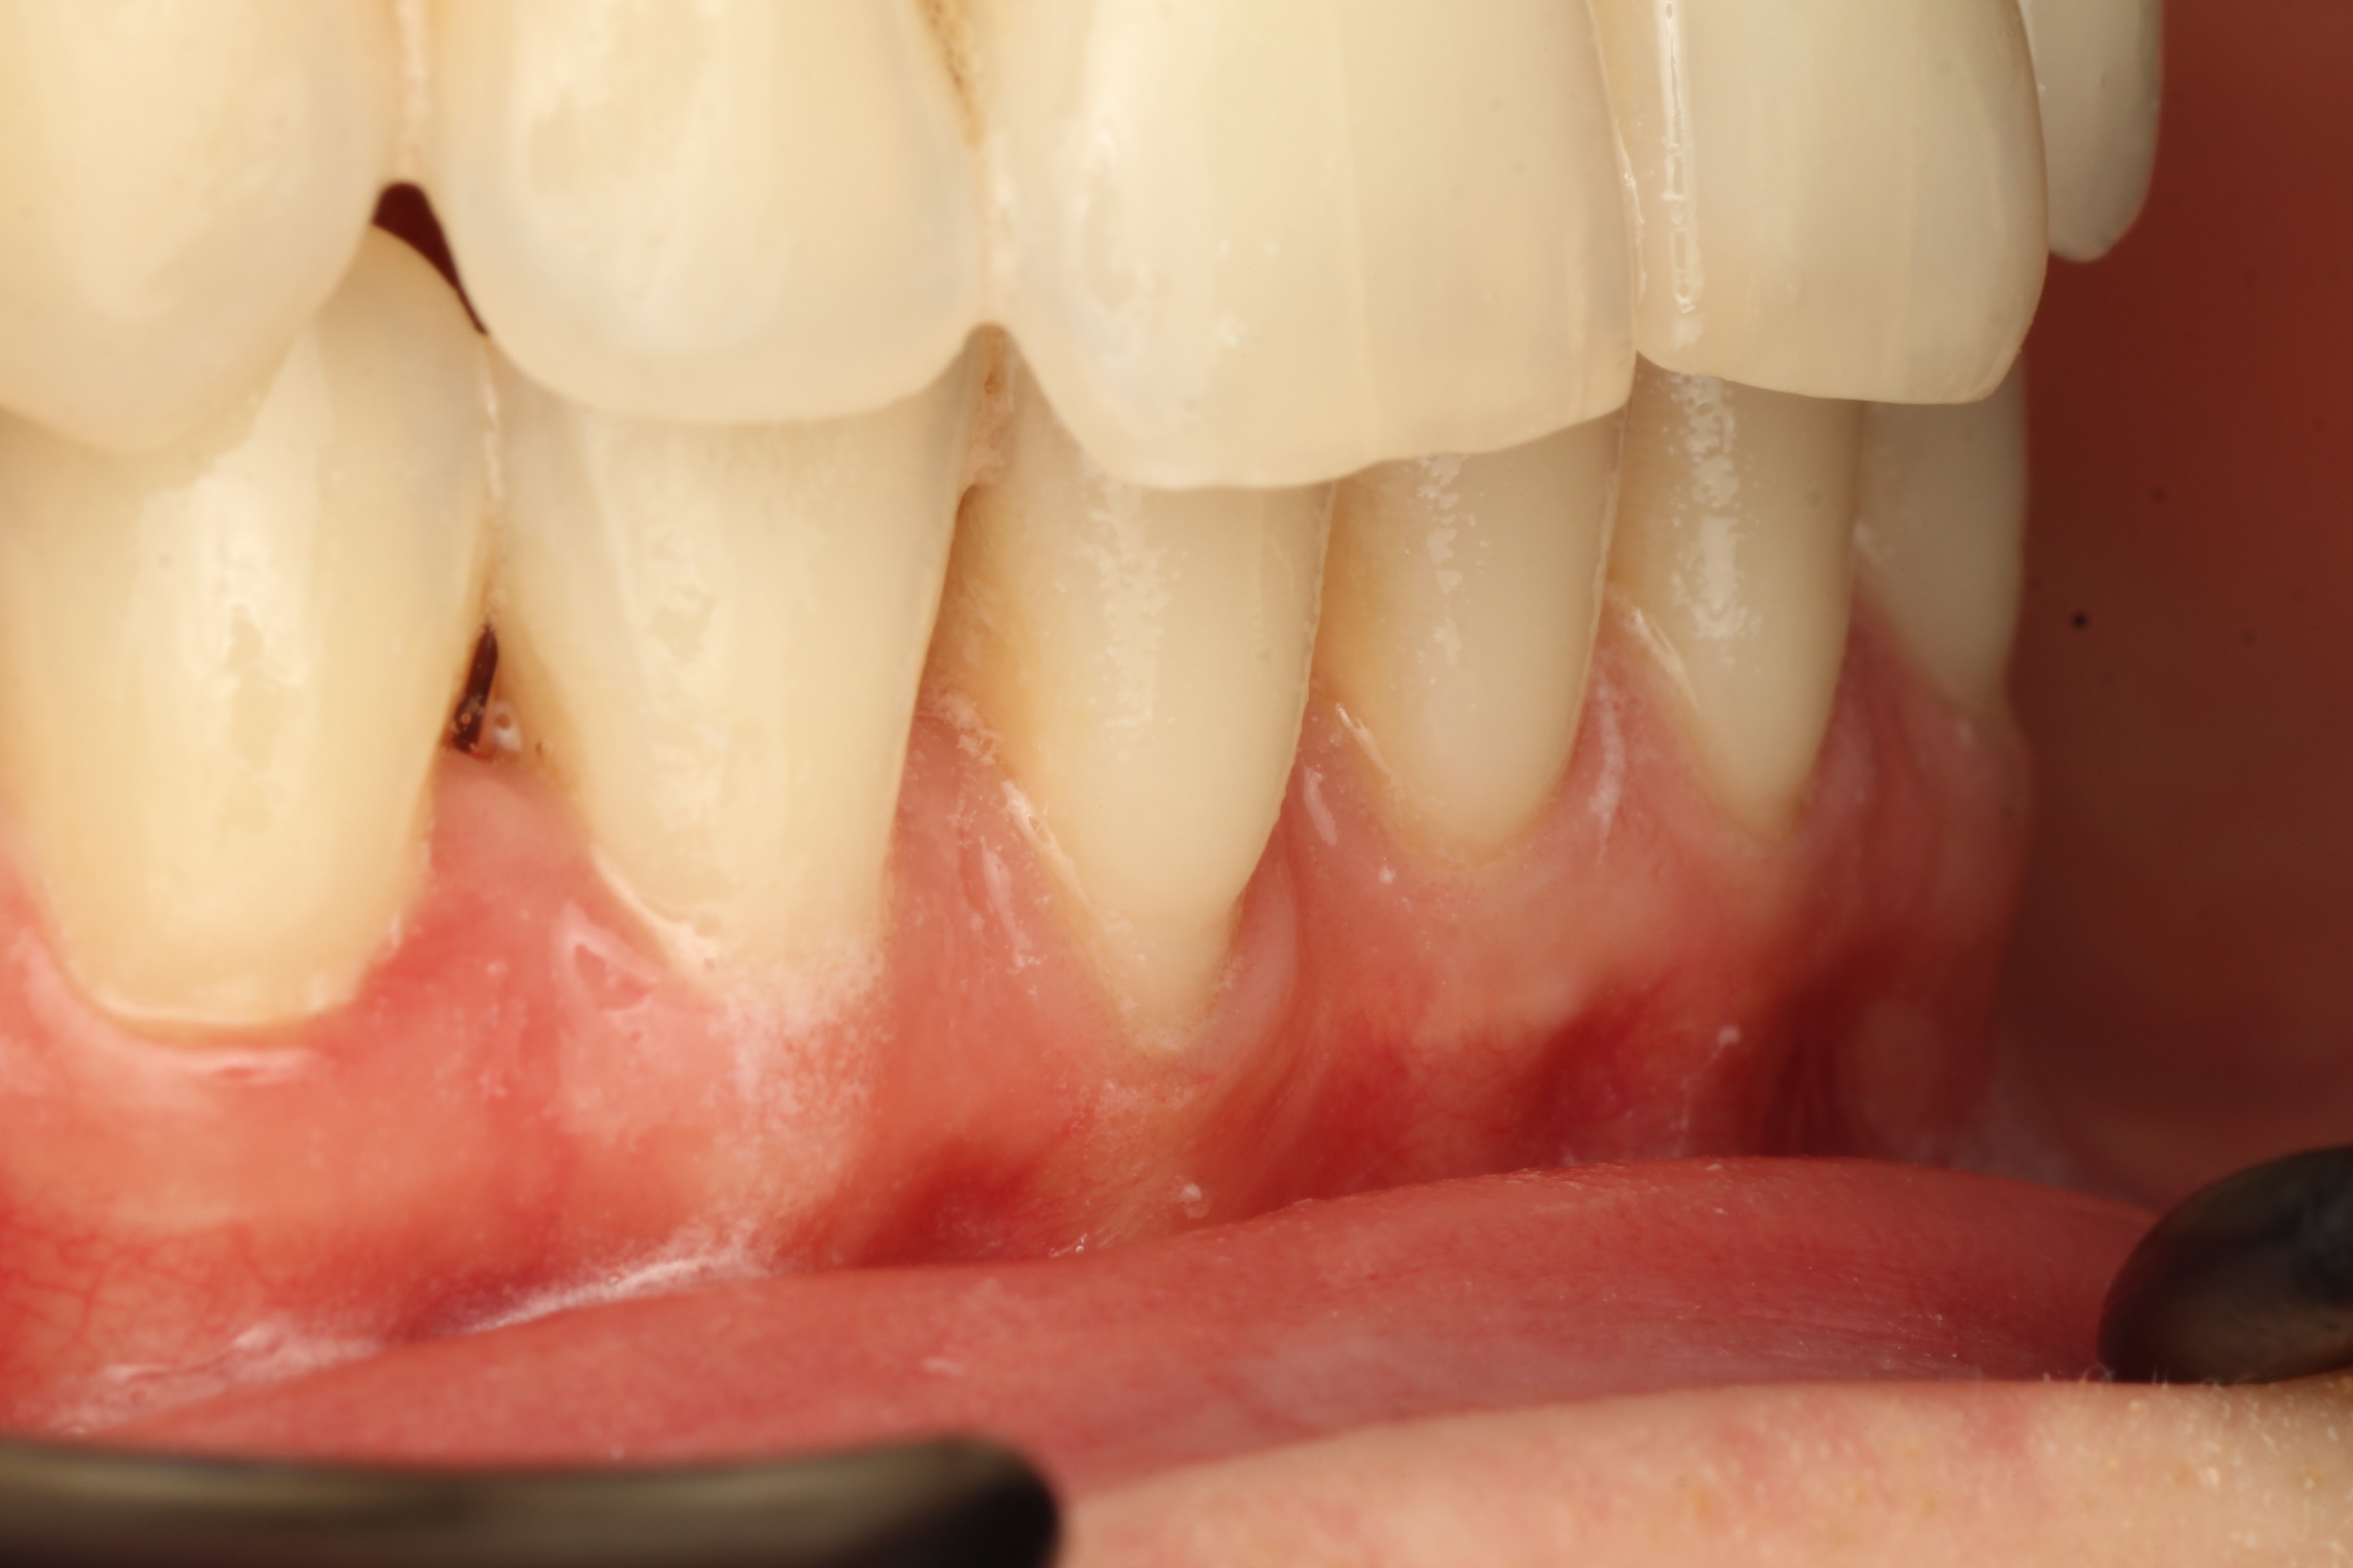

тонкий биотип десны, рецессия 2 мм на зубе 4.1

на фотографии в боковой проекции четко видны границы оголенного корня